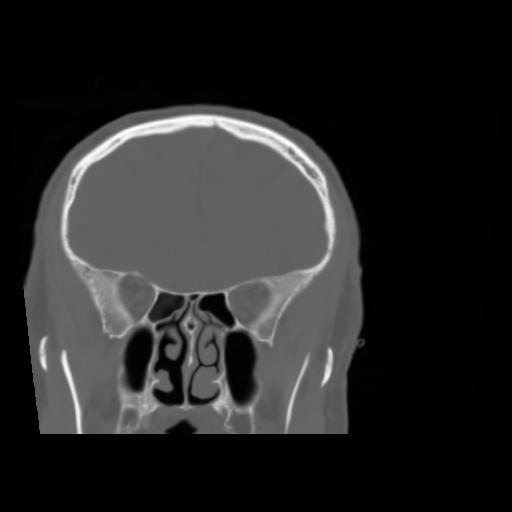

5 CEREBRO,,Coronal,3.000,CEREBRO,Coronal,